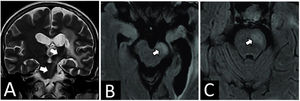

Resonancia magnética cerebral. A) Corte coronal, en secuencia en T2, con señal hiperintensa en la vía cortico espinal izquierda (flechas blancas), compatible con degeneración walleriana en tercera fase. B) En la secuencia FLAIR se observa hiperintensidad a nivel del pie del pedúnculo cerebral izquierdo (obsérvese el III nervio craneal hiperintenso). C) En la secuencia FLAIR, a nivel del pie protuberancial izquierdo.

La afectación de la vía corticoespinal puede presentarse a diferentes niveles, habitualmente con síntomas de hemiparesia faciobraquiocrural; en la ubicación mesencefálica con III nervio craneal ipsilateral afectado, y en protuberancia con VII nervio craneal y hemiparesia contralateral6. En el caso aquí presentado, la vía corticoespinal se vio afectada desde el lóbulo frontal hasta la protuberancia (fig. 3). En su paso por el mesencéfalo configuró un característico síndrome alterno de Weber.

La RM se correlaciona con cambios histológicos y metabólicos, clásicamente estudiados en pacientes post accidentes cerebrovasculares, ya que post radioterapia es escasa. Se describe que, en la primera fase, no suele haber signos. En la segunda fase, desde el día 20 hasta dos a cuatro meses, resulta en una señal hipointensa en secuencias de tiempo de repetición largo e identificándose mejor en secuencia densidad protónica por el mejor contraste con el fondo de sustancia blanca íntegra. En la tercera fase, la reabsorción de lípidos, gliosis y cambios en el contenido produce aumento de señal en secuencia T2 y FLAIR. En la cuarta fase o fase final, tras varios años existe una pérdida de volumen por atrofia que puede observarse en secuencias morfológicas20 relacionando con el caso, por presentar alta señal en FLAIR y en T2, se asume que el paciente es equivalente a encontrarse en la tercera fase de DW, teniendo un daño permanente de la vía cortico espinal (fig. 3).